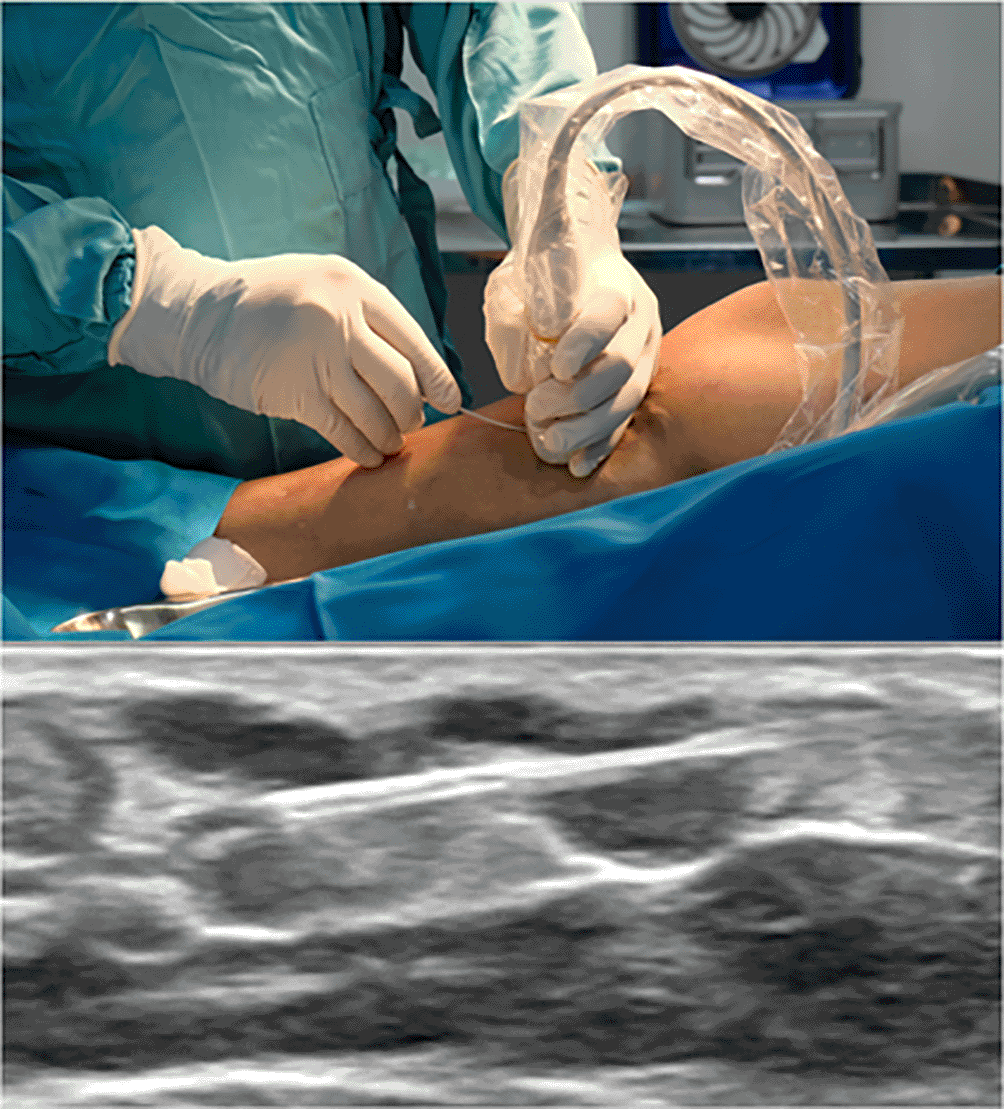

The procedure was ablation with Utoh’s technique using radial slim-type fiber and curved-like 16G IV catheter (Figure 1). After GSV ablation, we punctured the varicose vein with the ultrasound-guided method and inserted the fiber into the lumen (Figure 2). The energy used for varicose ablation was 3 watts with 20 Joule. With a similar technique, the fiber was slowly withdrawn with the speed of 0,14 cm/s (one panel in 7 s).

Figure 1. Bending Technique for Needle Puncture.

Figure 2. IV Cath Insertion Guided with Ultrasound.

For our patient, after the regular procedure, we punctured the varicose using Utoh’s ablation technique under ultrasound guidance with a 16 G needle; then the slim radial fiber was inserted without using any sheath. A tumescent solution was given to protect the surrounding tissue. Low energy was used to ablate the varicose because the diameter was 3 mm; the energy should be set based on diameter according to the latest study.17